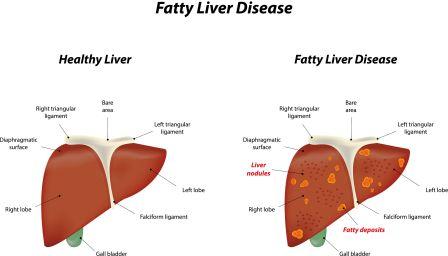

Liver is located in the right upper part of abdomen, its upper surface being just below your right lung (right chest cage) separated by a muscular layer called diaphragm. A part of right rib cage protects your upper part of liver.

It is a condition in which the liver cells accumulate abnormally increased amounts of fat. Excessive consumption of alcohol is a very common cause of Fatty Liver.

FLD is associated with other diseases that influence fat metabolism. When this process of fat metabolism is disrupted, the fat can accumulate in the liver in excessive amounts, thus resulting in fatty liver. Accumulation of fat may also be accompanied by a progressive inflammation of the liver (hepatitis) called steato-hepatitis.

- Hepatomegaly (your liver may get larger in size than normal)

Liver Cirrhosis

If you have FLD or ALD, you may get Liver Cirrhosis (scarring of liver). When the liver disease is far advanced (cirrhosis), signs and symptoms of cirrhosis predominate. They are as said below:

In both Fatty liver and NASH, there is an abnormal quantity of fat accumulation in the liver cells. In addition, in NASH there is inflammation of liver. As a result, the liver cells are damaged. The liver cells die and are replaced by scar tissue.

- All these events eventually lead to the accumulation of excessive fat in the liver leading to FLD.

Pathology of fatty liver

Fatty changes represent the accumulation of triglycerides (neutral fats) in the cytoplasm of liver cells.

- Late stages: Size of the vacuoles increases, nucleus is pushed to the periphery of the cell giving a characteristic ‘signet ring’ appearance (macro-vescicular fatty change). These vesicles are well delineated and optically empty because fats dissolve during tissue processing. Large vacuoles may coalesce and produce fatty cysts which are irreversible lesions.

- Macro-vescicular steatosis is the most common form. It is typically associated with alcohol, diabetes, obesity and corticosteroids.

- ASH, NASH and FLD progression: Severe fatty liver is sometimes accompanied by inflammation (steatohepatitis). Progression to alcoholic steatohepatitis (ASH) or Non-Alcoholic Steatohepatitis (NASH) depends on the persistence or severity of the inciting cause. Pathological lesions in both conditions are similar. The extent of inflammatory response varies widely and does not always correlate with degree of fat accumulation. Steatosis (retention of lipid or fat) and onset of steato-hepatitis may represent successive stages in FLD progression.

- Progression to Hepatic fibrosis: Liver disease with extensive inflammation and high degree of steatosis often progresses to more severe forms of disease. Hepatocyte ballooning and necrosis of varying degrees are often present at this stage.

Liver cell death and inflammatory responses lead to the activation of stellate cells, which play a pivotal role in hepatic fibrosis. The extent of fibrosis varies widely. Perisinusoidal fibrosis is most common, especially in adults and predominates in zone3 around the terminal hepatic veins

- Progression to cirrhosis: The progression to cirrhosis may be influenced by the amount of fat and degree of steato-hepatitis by a variety of other sensitizing factors. In alcoholic FLD the transition to cirrhosis related to continued alcohol consumption is well documented, but the process involved in non-alcoholic FLD is less clear